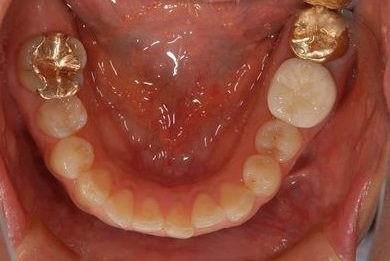

インプラント治療+セラミック治療+歯肉歯槽骨整形

| 性別/年齢 | 女性 / 38歳 | ||||||||||||||||||||||||||||||||

| 主訴 | 右下奥の欠損のため、インプラントを希望。また、左に物が挟まりやすいための治療も希望。 | ||||||||||||||||||||||||||||||||

| 治療内容 | インプラント1本、ジルコニアフレームオールセラミッククラウン2本(ジルコニアセラミック用土台1本)、歯肉歯槽骨整形 | ||||||||||||||||||||||||||||||||

| 総治療費 | 713,580円 | ||||||||||||||||||||||||||||||||

| 治療期間 | 10ヶ月 |